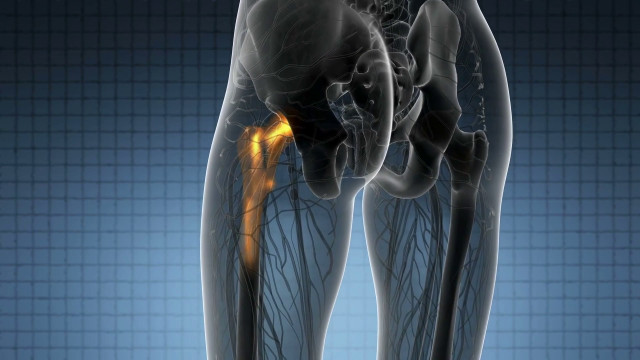

ROMA (ITALPRESS) – Le infezioni associate alle protesi aumentano il rischio di rigetto, compromettendo la salute del paziente e contribuendo al crescente problema della resistenza antimicrobica. I trattamenti standard che prevedono un’assunzione prolungata di antibiotici spesso si rivelano inutili contro queste comunità batteriche resistenti. Bioaction è un progetto finanziato dalla Commissione Europea che mira a rivoluzionare l’approccio alle infezioni batteriche che spesso accompagnano le protesi mediche.